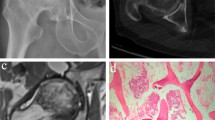

There were 23 NTONFH patients and 22 healthy controls included eventually with 27 patients (21 classfied Ficat III or IV, four influenced by recent NSAIDs intake, one accompanied with rheumatoid arthritis, and one with uncertain history of trauma) and three controls (with abnormal levels of both ESR and CRP) excluded. No statistical significance was detected in terms of age (NTONFH 51.86 ± 12.2, control 53.43 ± 16.78, p = 0.72), sex (NTONFH 16M + 6F, control 15M + 8F, p = 0.75), or BMI (NTONFH 23.23 ± 3.27, control 24.53 ± 3.64, p = 0.22) between the two groups. Image manifestations of the two groups were displayed in Fig. 1.